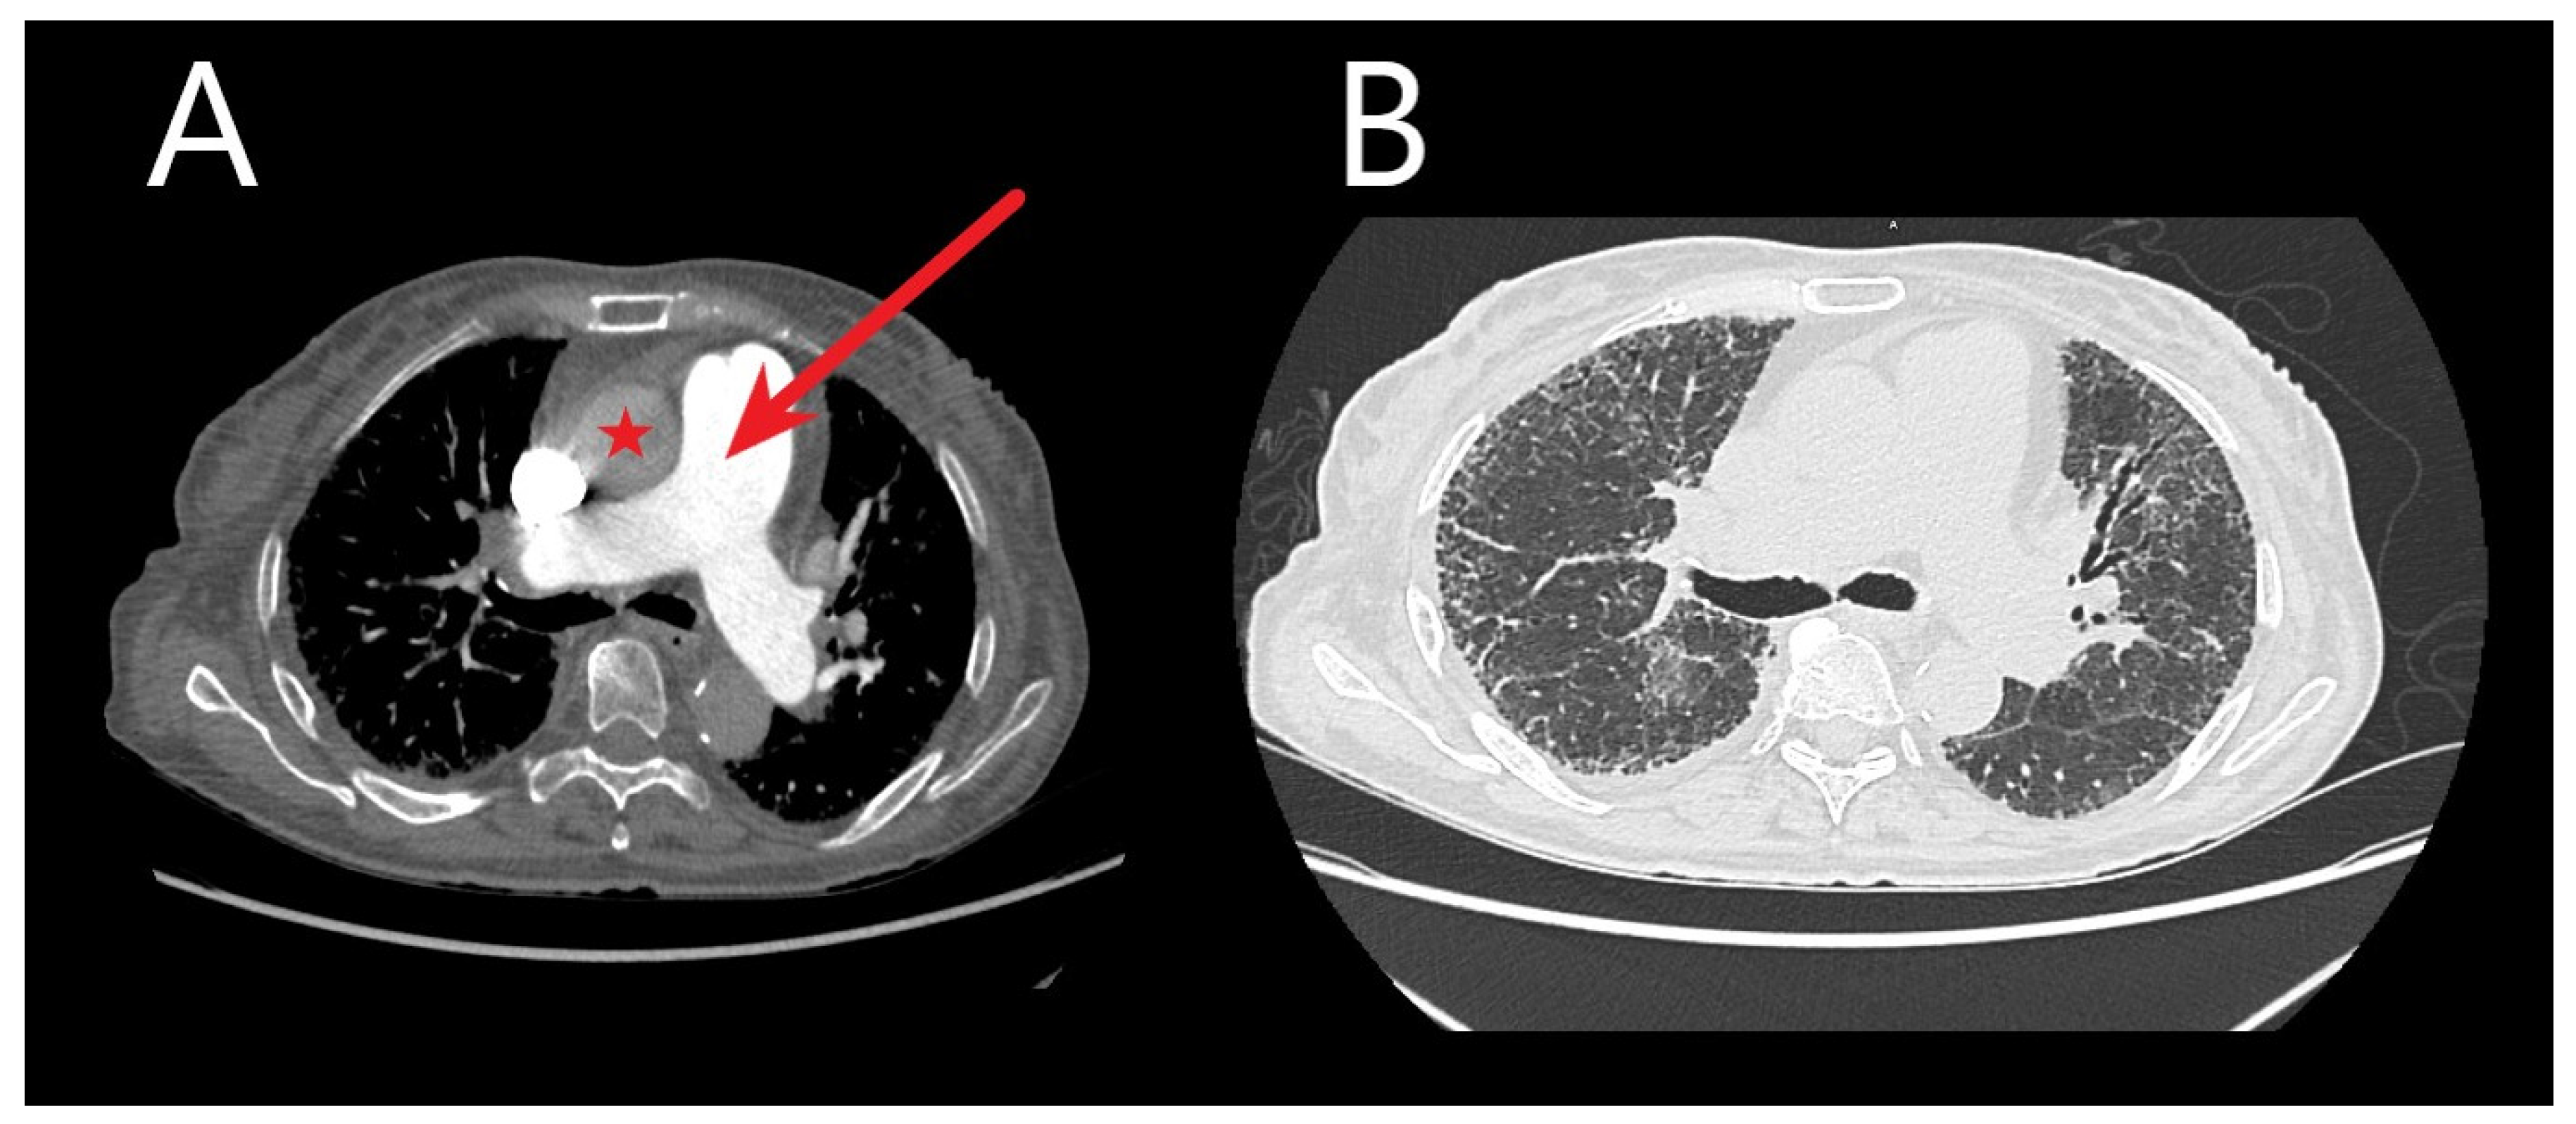

6.4. Chest Computed Tomography

- Goerne, H.; Batra, K.; Rajiah, P. Imaging of pulmonary hypertension: An update. Cardiovasc. Diagn. Ther. 2018, 8, 279–296. [Google Scholar] [CrossRef] [PubMed]

- Foley, R.W.; Kaneria, N.; Ross, R.V.M.; Suntharalingam, J.; Hudson, B.J.; Rodrigues, J.C.; Robinson, G. Computed tomography appearances of the lung parenchyma in pulmonary hypertension. Br. J. Radiol. 2021, 94, 20200830. [Google Scholar] [CrossRef]

- Chen, R.; Liao, H.; Deng, Z.; He, Z.; Zheng, Z.; Lu, J.; Jiang, M.; Wu, X.; Guo, W.; Huang, Z.; et al. Efficacy of computed tomography in diagnosing pulmonary hypertension: A systematic review and meta-analysis. Front. Cardiovasc. Med. 2022, 9, 966257. [Google Scholar] [CrossRef]

- Tan, R.T.; Kuzo, R.; Goodman, L.R.; Siegel, R.; Haasler, G.R.; Presberg, K.W. Utility of CT Scan Evaluation for Predicting Pulmonary Hypertension in Patients With Parenchymal Lung Disease. Chest 1998, 113, 1250–1256. [Google Scholar] [CrossRef]

- Swift, A.J.; Dwivedi, K.; Johns, C.; Garg, P.; Chin, M.; Currie, B.J.; Rothman, A.M.; Capener, D.; Shahin, Y.; Elliot, C.A.; et al. Diagnostic accuracy of CT pulmonary angiography in suspected pulmonary hypertension. Eur. Radiol. 2020, 30, 4918–4929. [Google Scholar] [CrossRef] [PubMed]

- Shen, Y.; Wan, C.; Tian, P.; Wu, Y.; Li, X.; Yang, T.; An, J.; Wang, T.; Chen, L.; Wen, F. CT-Base Pulmonary Artery Measurementin the Detection of Pulmonary Hypertension: A Meta-Analysis and Systematic Review. Medicine 2014, 93, e256. [Google Scholar] [CrossRef] [PubMed]

- Zisman, D.A.; Karlamangla, A.S.; Ross, D.J.; Keane, M.P.; Belperio, J.A.; Saggar, R.; Lynch, J.P.; Ardehali, A.; Goldin, J. High-Resolution Chest CT Findings Do Not Predict the Presence of Pulmonary Hypertension in Advanced Idiopathic Pulmonary Fibrosis. Chest 2007, 132, 773–779. [Google Scholar] [CrossRef] [PubMed]

- Matsushita, S.; Matsuoka, S.; Yamashiro, T.; Fujikawa, A.; Yagihashi, K.; Kurihara, Y.; Nakajima, Y. Pulmonary arterial enlargement in patients with acute exacerbation of interstitial pneumonia. Clin. Imaging 2014, 38, 454–457. [Google Scholar] [CrossRef] [PubMed]

- Sharma, M.; Burns, A.T.; Yap, K.; Prior, D.L. The role of imaging in pulmonary hypertension. Cardiovasc. Diagn. Ther. 2021, 11, 859–880. [Google Scholar] [CrossRef] [PubMed]

- Scelsi, C.L.; Bates, W.B.; Melenevsky, Y.V.; Sharma, G.K.; Thomson, N.B.; Keshavamurthy, J.H. Egg-and-Banana Sign: A Novel Diagnostic CT Marker for Pulmonary Hypertension. Am. J. Roentgenol. 2018, 210, 1235–1239. [Google Scholar] [CrossRef]

- Frazier, A.A.; Burke, A.P. The Imaging of Pulmonary Hypertension. Semin. Ultrasound CT MRI 2012, 33, 535–551. [Google Scholar] [CrossRef]

- Kiely, D.G.; Levin, D.L.; Hassoun, P.M.; Ivy, D.; Jone, P.; Bwika, J.; Kawut, S.M.; Lordan, J.; Lungu, A.; Mazurek, J.A.; et al. Statement on imaging and pulmonary hypertension from the Pulmonary Vascular Research Institute (PVRI). Pulm. Circ. 2019, 9, 1–32. [Google Scholar] [CrossRef]